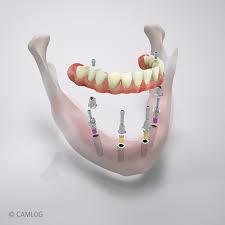

Alle Zähne fehlen

Ursprünglich sollten Zähne wohl ein Leben lang halten. Doch die Realität sieht anders aus. Gut, dass Implantate eine sichere und komfortable Lösung bieten. Sie können wieder ganz natürlich essen, reden und lachen – als ob es Ihre “Zweiten” wären. Schon zwei bis vier der kleinen Titan-Wurzeln reichen aus, um einer Vollprothese festen Halt zu geben. Auf sechs Implantaten kann bereits eine Brücke dauerhaft befestigt werden. Egal, für welche Lösung Sie sich entscheiden: Zuverlässige Stabilität im Ober- wie im Unterkiefer garantiert Ihnen hohe Sicherheit und ein gutes Gefühl – in jedem Alter und bei nahezu jeder Ausgangssituation.

Ideale Version

Die meisten Zähne werden mit vielen Implantaten ersetzt.

Economy Version

Einige Zähne werden mit Implantaten ersetzt.

Wackelige Prothesen und schmerzende Druckstellen? Mit Implantaten von Camlog gehört das der Vergangenheit an. Ihre “neuen Zähne” funktionieren genauso wie Ihre natürlichen Vorgänger und sitzen zuverlässig und fest im Kiefer – nichts kann sich verschieben oder verrutschen. Entscheiden Sie sich für eine dauerhafte Fixierung Ihrer Brücke, kann auf den rosafarbenen Prothesenkunststoff ganz verzichtet werden. Eigene Zähne bleiben erhalten und können harmonisch in den Zahnersatz integriert werden. Implantate von Camlog sind der natürlichen Zahnwurzel nachempfunden. So werden Knochen und Zahnfleisch richtig belastet und bleiben erhalten.

Das MDI Sendax System (Mini-Dental-Implantat) sorgt bei uns und unseren Patienten für Begeisterung. In nur einer Sitzung erreichen wir einen sofortbelastbaren und sicheren Sitz von totalen Prothesen, bei einem großartigen Preis- Leistungsverhältnis.

Dazu werden im Unterkiefer 4, im Oberkiefer 6 Implantate benötigt. Das MDI System ist das einzige Mini-Implantat mit FDA-Zulassung für die Langzeitstabilisierung von Zahnersatz.

Das Mini-Dental-Implantat (MDI) ist eine 1,8 bis 2,4 mm dicke Titanschraube mit einem Kugelkopf. Diese Schraube wird mit normaler Betäunbung, meist ohne Eröffnung der Schleimhaut und dadurch ohne Wunde (minimalinvasiv) in den Knochen eingebracht. Im Anschluß daran werden die speziellen Halteelemente in die Prothese eingearbeitet. Diese Halteelemente sorgen für den sicheren Sitz des Zahnersatzes und gleichzeitig als Stoßdämpfer gegenüber dem Knochen.